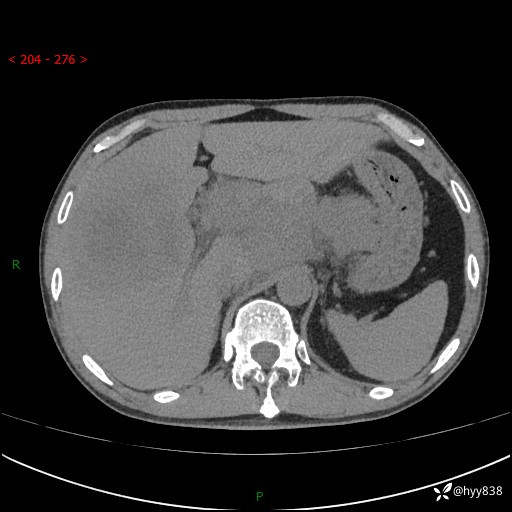

上腹部CT平扫+增强(两期)